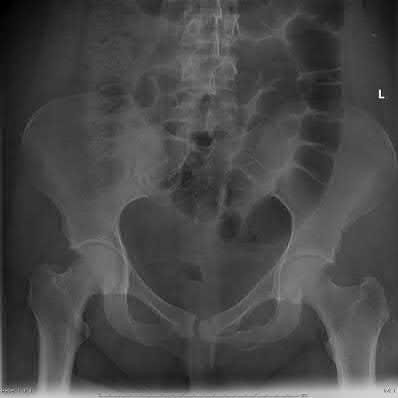

A 35 year-old female presents after prolonged extrication from a motor vehicle collision complaining of severe pelvic pain. Physical examination reveals diminished perianal sensation. She is otherwise neurologically intact. Figures A through D are radiographs and representative CT cuts of her injury. Which of the following nerve roots has likely been injured by the acute trauma?

The clinical scenario is consistent with a high-energy sacral fracture. The radiographs in figures A and B demonstrate a sacral fracture with posterior displacement of the right hemipelvis seen on the inlet view. Figures C and D are axial and sagittal CT images which show a displaced fracture of the right

hemisacrum along with a transvere fracture component through the S3 body . Diminished perianal sensation is concerning for an S2 nerve root injury.

Mehta et al reviewed the current management of sacral fractures. They note that the S1 and S2 nerve roots are more likely to be injured with sacral fractures as they occupy 1/3 to 1/4 of the neural foramina, as opposed to S3 and S4, which only occupy 1/6 of the neural foramina.

Robles reviewed the current literature to ascertain principles of evaluation and treatment for transverse sacral fractures. The author notes that injury to nerve roots S2 to S5 is manifested by impairment of urinary and anal continence and sexual function.

The first illustration demonstrates the sacral nerve root dermatomal distribution. The second shows a pelvic cadaver dissection demonstrating the sacral nerve roots as they exit the foramina.